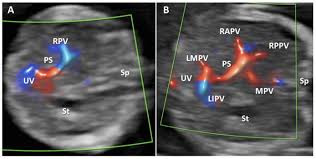

- 간내 혈관 기형